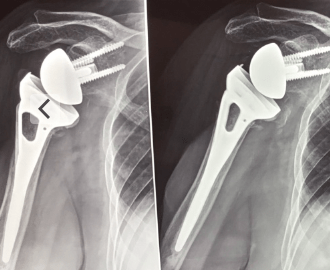

Cos’e’ una protesi di spalla

La protesi di spalla è un’opzione terapeutica per il trattamento delle patologie della spalla che non rispondono alla terapia conservativa. E’ fondamentale intervenire precocemente poiché il protrarsi dell’attesa contribuisce ad una minore elasticità dei tessuti muscolo tendini e di conseguenza al rischio di compromettere il corretto funzionamento dell nuova articolazione protesica. Quando impiantare una protesi di spalla? La…